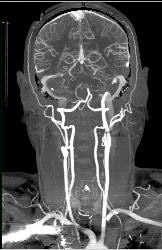

CTA With Dual Energy and Bone Removal